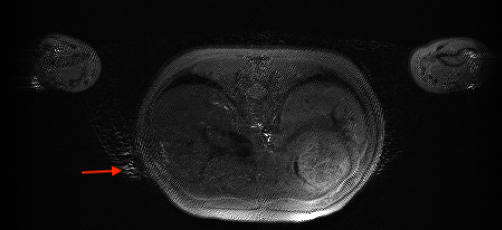

2.1 FID

- Appearance: fuzzy image as highlighted by the arrow

- Casue: FID signal in the RF180

- Solution: crusher, especially on the z-axis